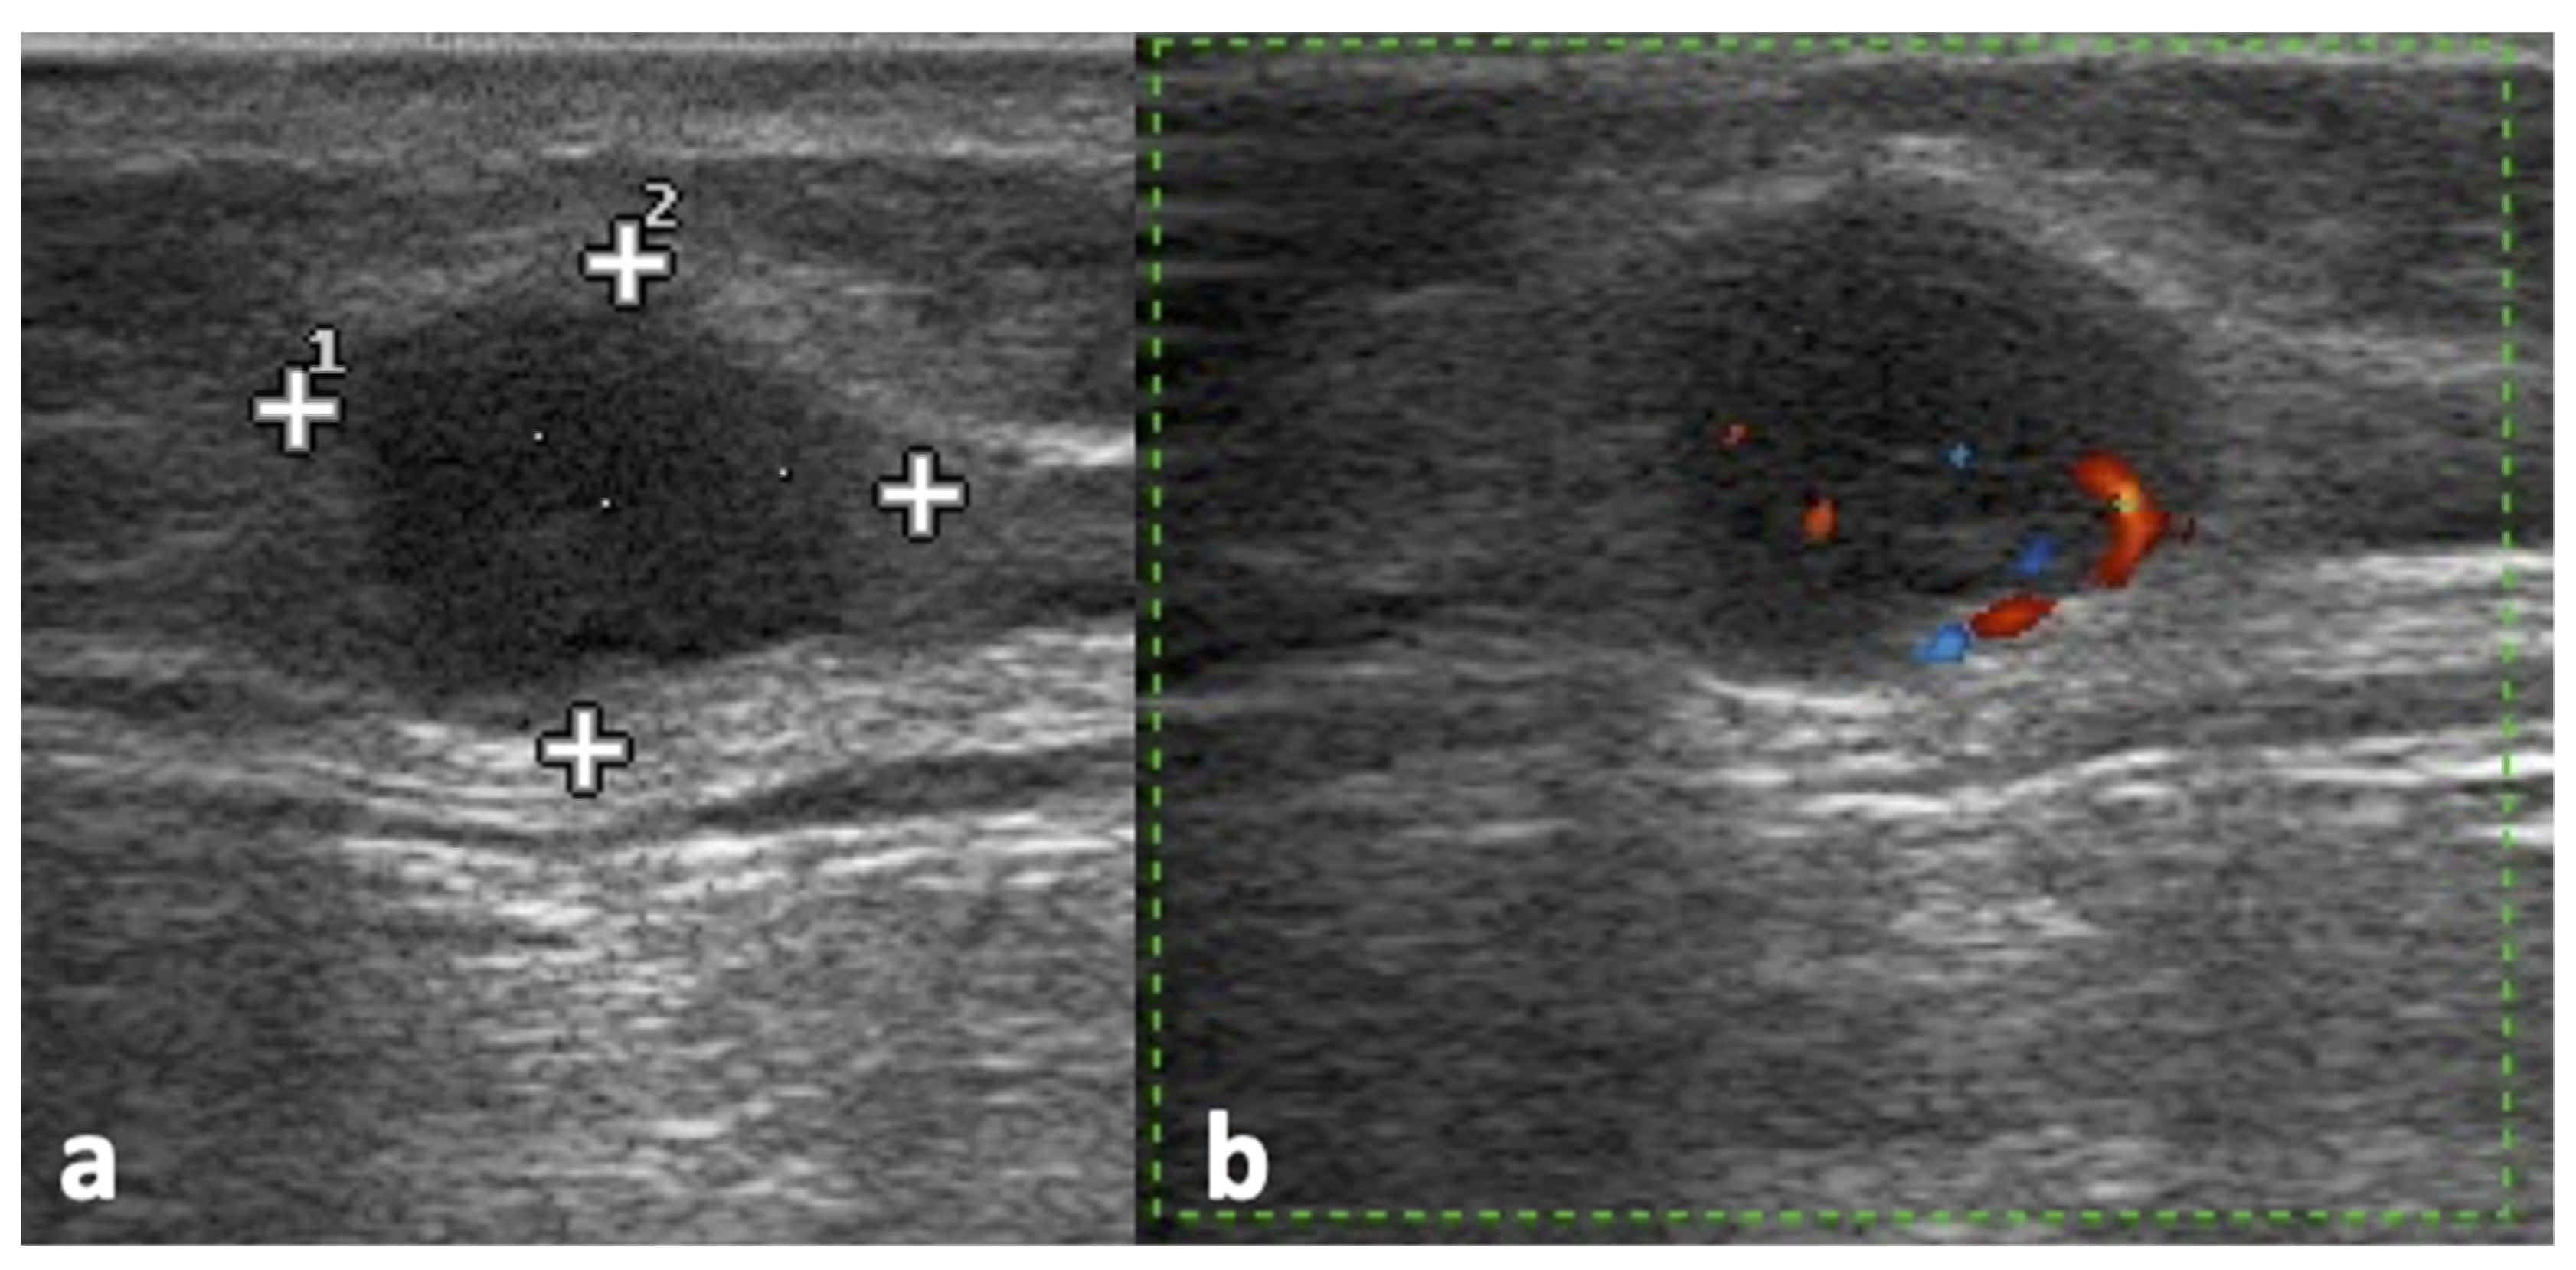

2.4. Ultrasound Assessment